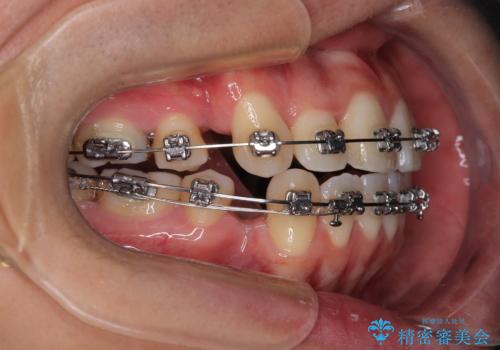

- 矯正装置

- メタルブラケット

- 治療期間

- 2年

抜歯したスペースを活用して前歯を後ろへ下げることで、口元の突出感を大きく改善。

奥歯の噛み合わせがずれている「シザーズバイト」を適正に整えることで、見た目だけでなく機能性も向上し、安定した咬合が獲得できました。